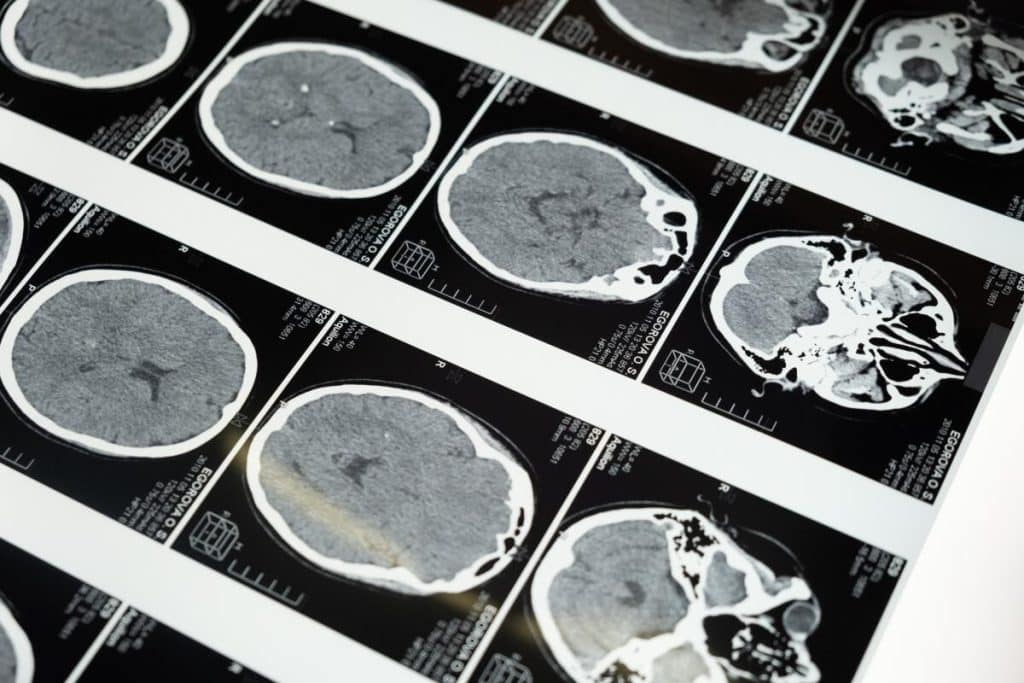

Dispozitivul, denumit „Isolda”, își propune să ofere o imagine extraordinar de detaliată a creierului uman, deschizând noi orizonturi în diagnosticarea și tratarea bolilor neurodegenerative și psihiatrice.

Având un câmp magnetic de 11,7 T (tesla), de zece ori mai puternic decât scanerele RMN din spitalele obișnuite, „Isolda” este rezultatul unei colaborări franco-germane și a peste două decenii de cercetare intensivă. Testele inițiale ale dispozitivului, care au implicat un dovleac ca obiect de studiu, au confirmat că acesta poate furniza imagini incredibil de precise ale structurii cerebrale umane.

Alexandre Vignaud, fizician și director de cercetare la Comisariatul pentru energie atomică și energii regenerabile din Franța (CEA), a subliniat nivelul de precizie fără precedent pe care „Isolda” îl oferă în imagistica cerebrală. El a comparat imaginile obținute cu cele produse de scanerele RMN tradiționale și a evidențiat capacitatea dispozitivului de a afișa detalii minuțioase, cum ar fi vasele mici de sânge care alimentează cortexul cerebral.